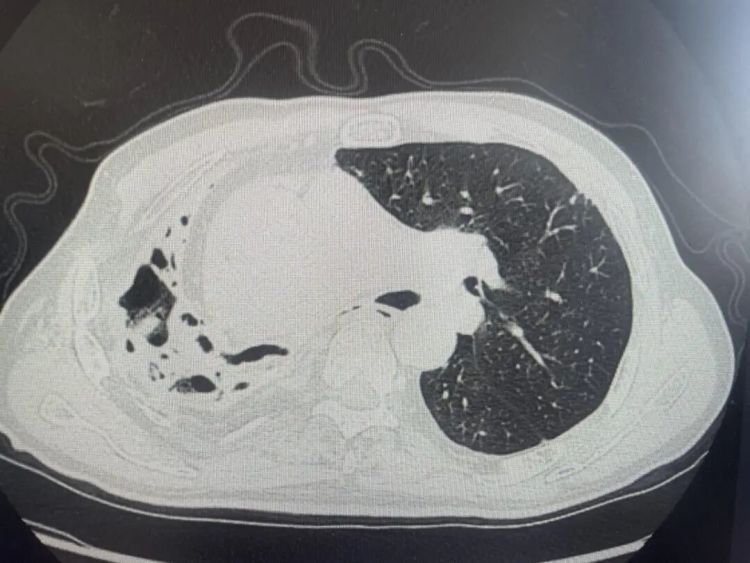

肺部CT结果显示,王大伯的右肺已严重毁损,呈现出典型的蜂窝状改变,肺功能受损严重。凭借丰富临床经验,医生高度怀疑是特殊致病菌感染,随即通过支气管镜肺泡灌洗,结合NGS高通量测序查找病原体。

肺部CT提示右肺毁损、蜂窝状改变